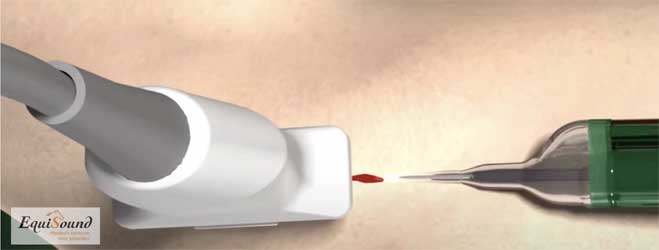

Préparation et réalisation d’un traitement Tenex échoguidé chez un cheval debout.

Tenex est une technique de traitement développée il y a 5 ans aux États-Unis pour traiter des pathologies tendineuses chroniques chez l’être humain (atteinte chronique des tendons d’Achille, épine calcanéenne, dégénérescence du tendon rotulien, etc.). Cette technique utilise des ultrasons (comme pour un détartrage) afin de détruire le tissu endommagé et de stimuler ainsi le processus de cicatrisation pour offrir une nouvelle chance de guérison. La fréquence ultrasonore est spécifiquement choisie pour ne détruire que les tissus durs (fibrose et minéralisations) et ne pas causer de dommages au tissu tendineux sain. Le traitement par ultrasons est appliqué à l’aide d’une aiguille creuse dans un tube creux (cf. photo 8a). Durant le traitement, un flux de NaCl sort de l’aiguille creuse et est simultanément aspiré via le tube creux (cf. photos 8b et 8c). Cette solution aqueuse permet avant tout l’évacuation du tissu débridé mais aussi le refroidissement de l’aiguille qui chauffe fortement en raison des ultrasons.